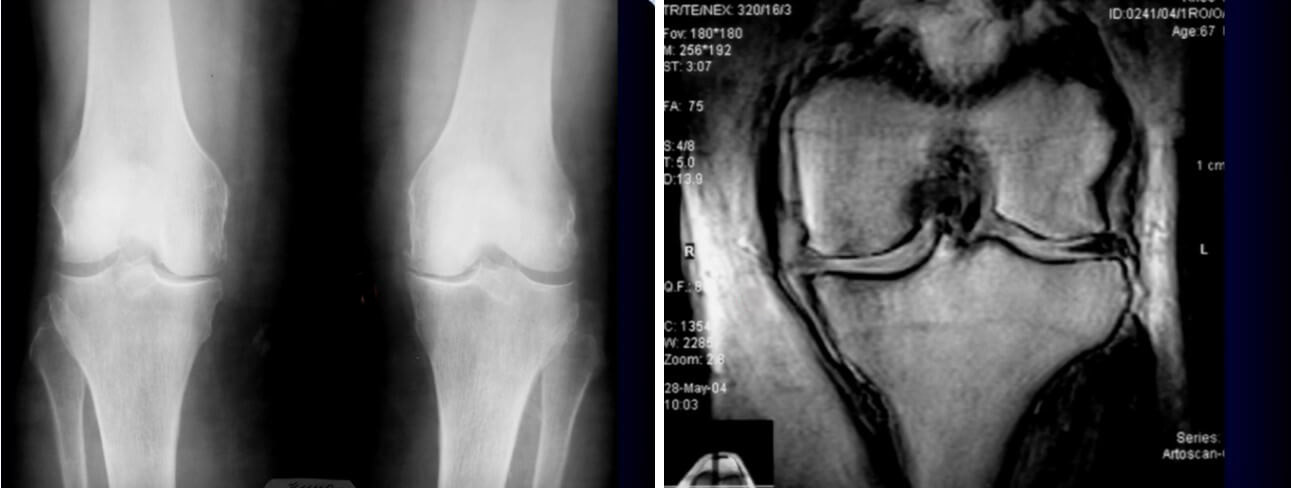

2-3 стадия остеоартрита. На рентгеновском снимке (слева) четко видны: неравномерное сужение суставной щели и остеофиты. На МРТ (справа): неравномерное сужение суставной щели в медиальном отделе, значительные изменения медиального мениска, коллатеральная связка неравномерно отходит от края кости

3-я стадия остеоартрита: неравномерное сужение суставной щели, остеофиты, субхондральный остеосклероз в месте наибольшего сужения суставной щели

Что можно увидеть на МРТ при 3-й стадии ОА коленного сустава?

- 1. Значительные по протяженности участки дегенерации и деструкции суставного хряща, возможно его полное отсутствие на определенных участках суставной поверхности – МРТ помогает визуализировать истинную структуру суставного хряща, его толщину, плотность и дефекты, рассчитать площадь его поражения. По рентгенограммам мы можем судить о состоянии хрящей опосредованно по высоте суставной щели и состоянию субхондральной кости,

- 2. Грубые дегенеративные изменения связок и фиброзно-хрящевых структур сустава (менисков)

- 3. Участки субхондрального фиброза костного мозга

- 4. Множественные краевые костные разрастания (остеофиты)

- 5. Выраженный отёк костного мозга

- 6. Синовит и поражение (разрастание) синовиальной оболочки

- 7. Изменения формы и размера костей, формирующих сустав

- 8. Разрастание фиброзной ткани в полости сустава

МРТ помогает не только подтвердить стадию ОА, но и считается незаменимой в предоперационном планировании при эндопротезировании сустава, а также, помогает определить причину боли в суставе и степень поражения мягких тканей.

4-я стадия: присутствие всех симптомов и выраженная варусная деформация. На МРТ: перестройка субхондральных структур и развитие асептического некроза, выраженные деформации суставных поверхностей.